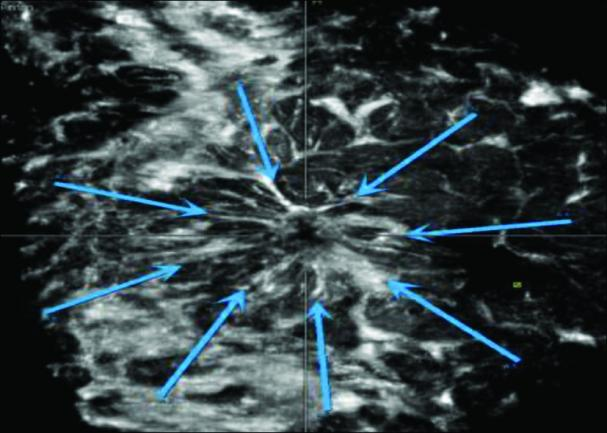

3.独特的冠状面成像:ABVS 比常规超声多了一个非常重要的冠状面成像,冠状面图像上的“汇聚征”对于诊断乳腺癌具有非常高的特异性,从而进一步提高了乳腺恶性肿瘤的早期检出率。ABVS 能提高超声对微钙化的检出率,特别是无肿块背景下的微钙化,ABVS 的冠状面成像能直观显示微钙化分布范围,提高超声对导管内癌的鉴别诊断能力。

上图:汇聚征

低回声肿块周边呈现向中心汇聚的放射状排列高回声。